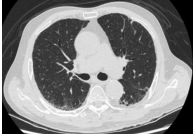

8.右胸痛 3 個月